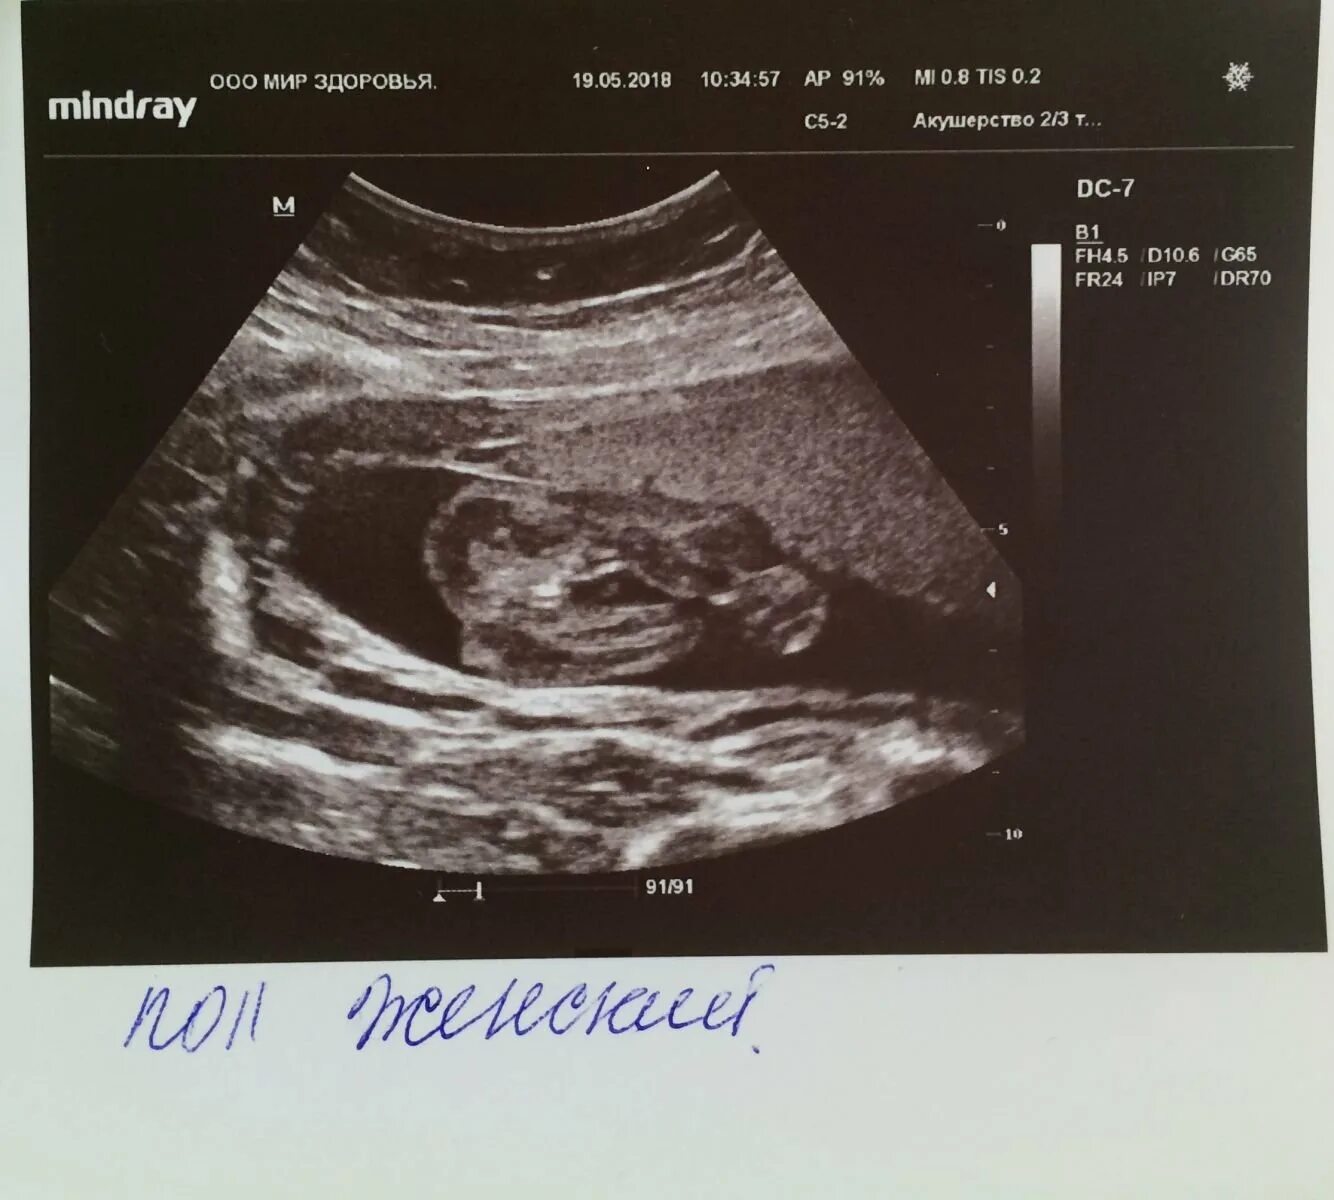

Может ли ошибки узи